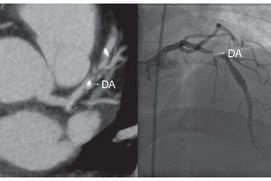

ANGIO TAC CORONARIA: Un avance en el diagnóstico cardiológico  | BCM

ANGIO TAC CORONARIA: Un avance en el diagnóstico cardiológico